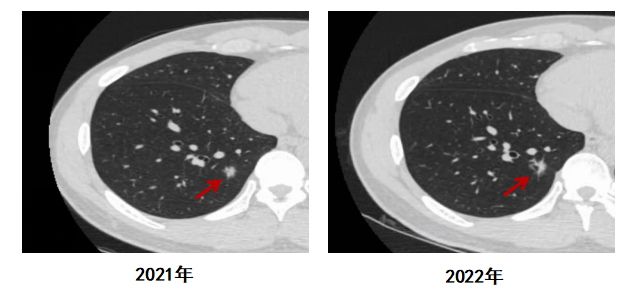

Y先生,46歲,吸煙20余年,平均1-2包/天,有肺癌家族史,無(wú)高危環(huán)境及職業(yè)接觸史及慢性肺部疾病史,2022年在單位體檢中發(fā)現(xiàn)右肺亞實(shí)性結(jié)節(jié),大小9mm×9mm,為肺結(jié)節(jié)紅色預(yù)警。工作人員電話告知他前往心胸外科就診,但他本人自覺(jué)沒(méi)什么不舒服,并未就診,也沒(méi)有在短期內(nèi)復(fù)查。

1年后單位體檢,Y先生的右肺結(jié)節(jié)較前增大,大小為12mm×9mm,可見(jiàn)棘突及軟長(zhǎng)毛刺伴鄰近胸膜稍牽拉,內(nèi)見(jiàn)小空腔形成。工作人員再次電話告知他存在高危肺結(jié)節(jié),建議就診。Y先生這才著急了,前往胸外科就診并住院手術(shù)治療,術(shù)后病理提示肺癌。好在經(jīng)過(guò)及時(shí)治療,Y先生身體恢復(fù)良好。